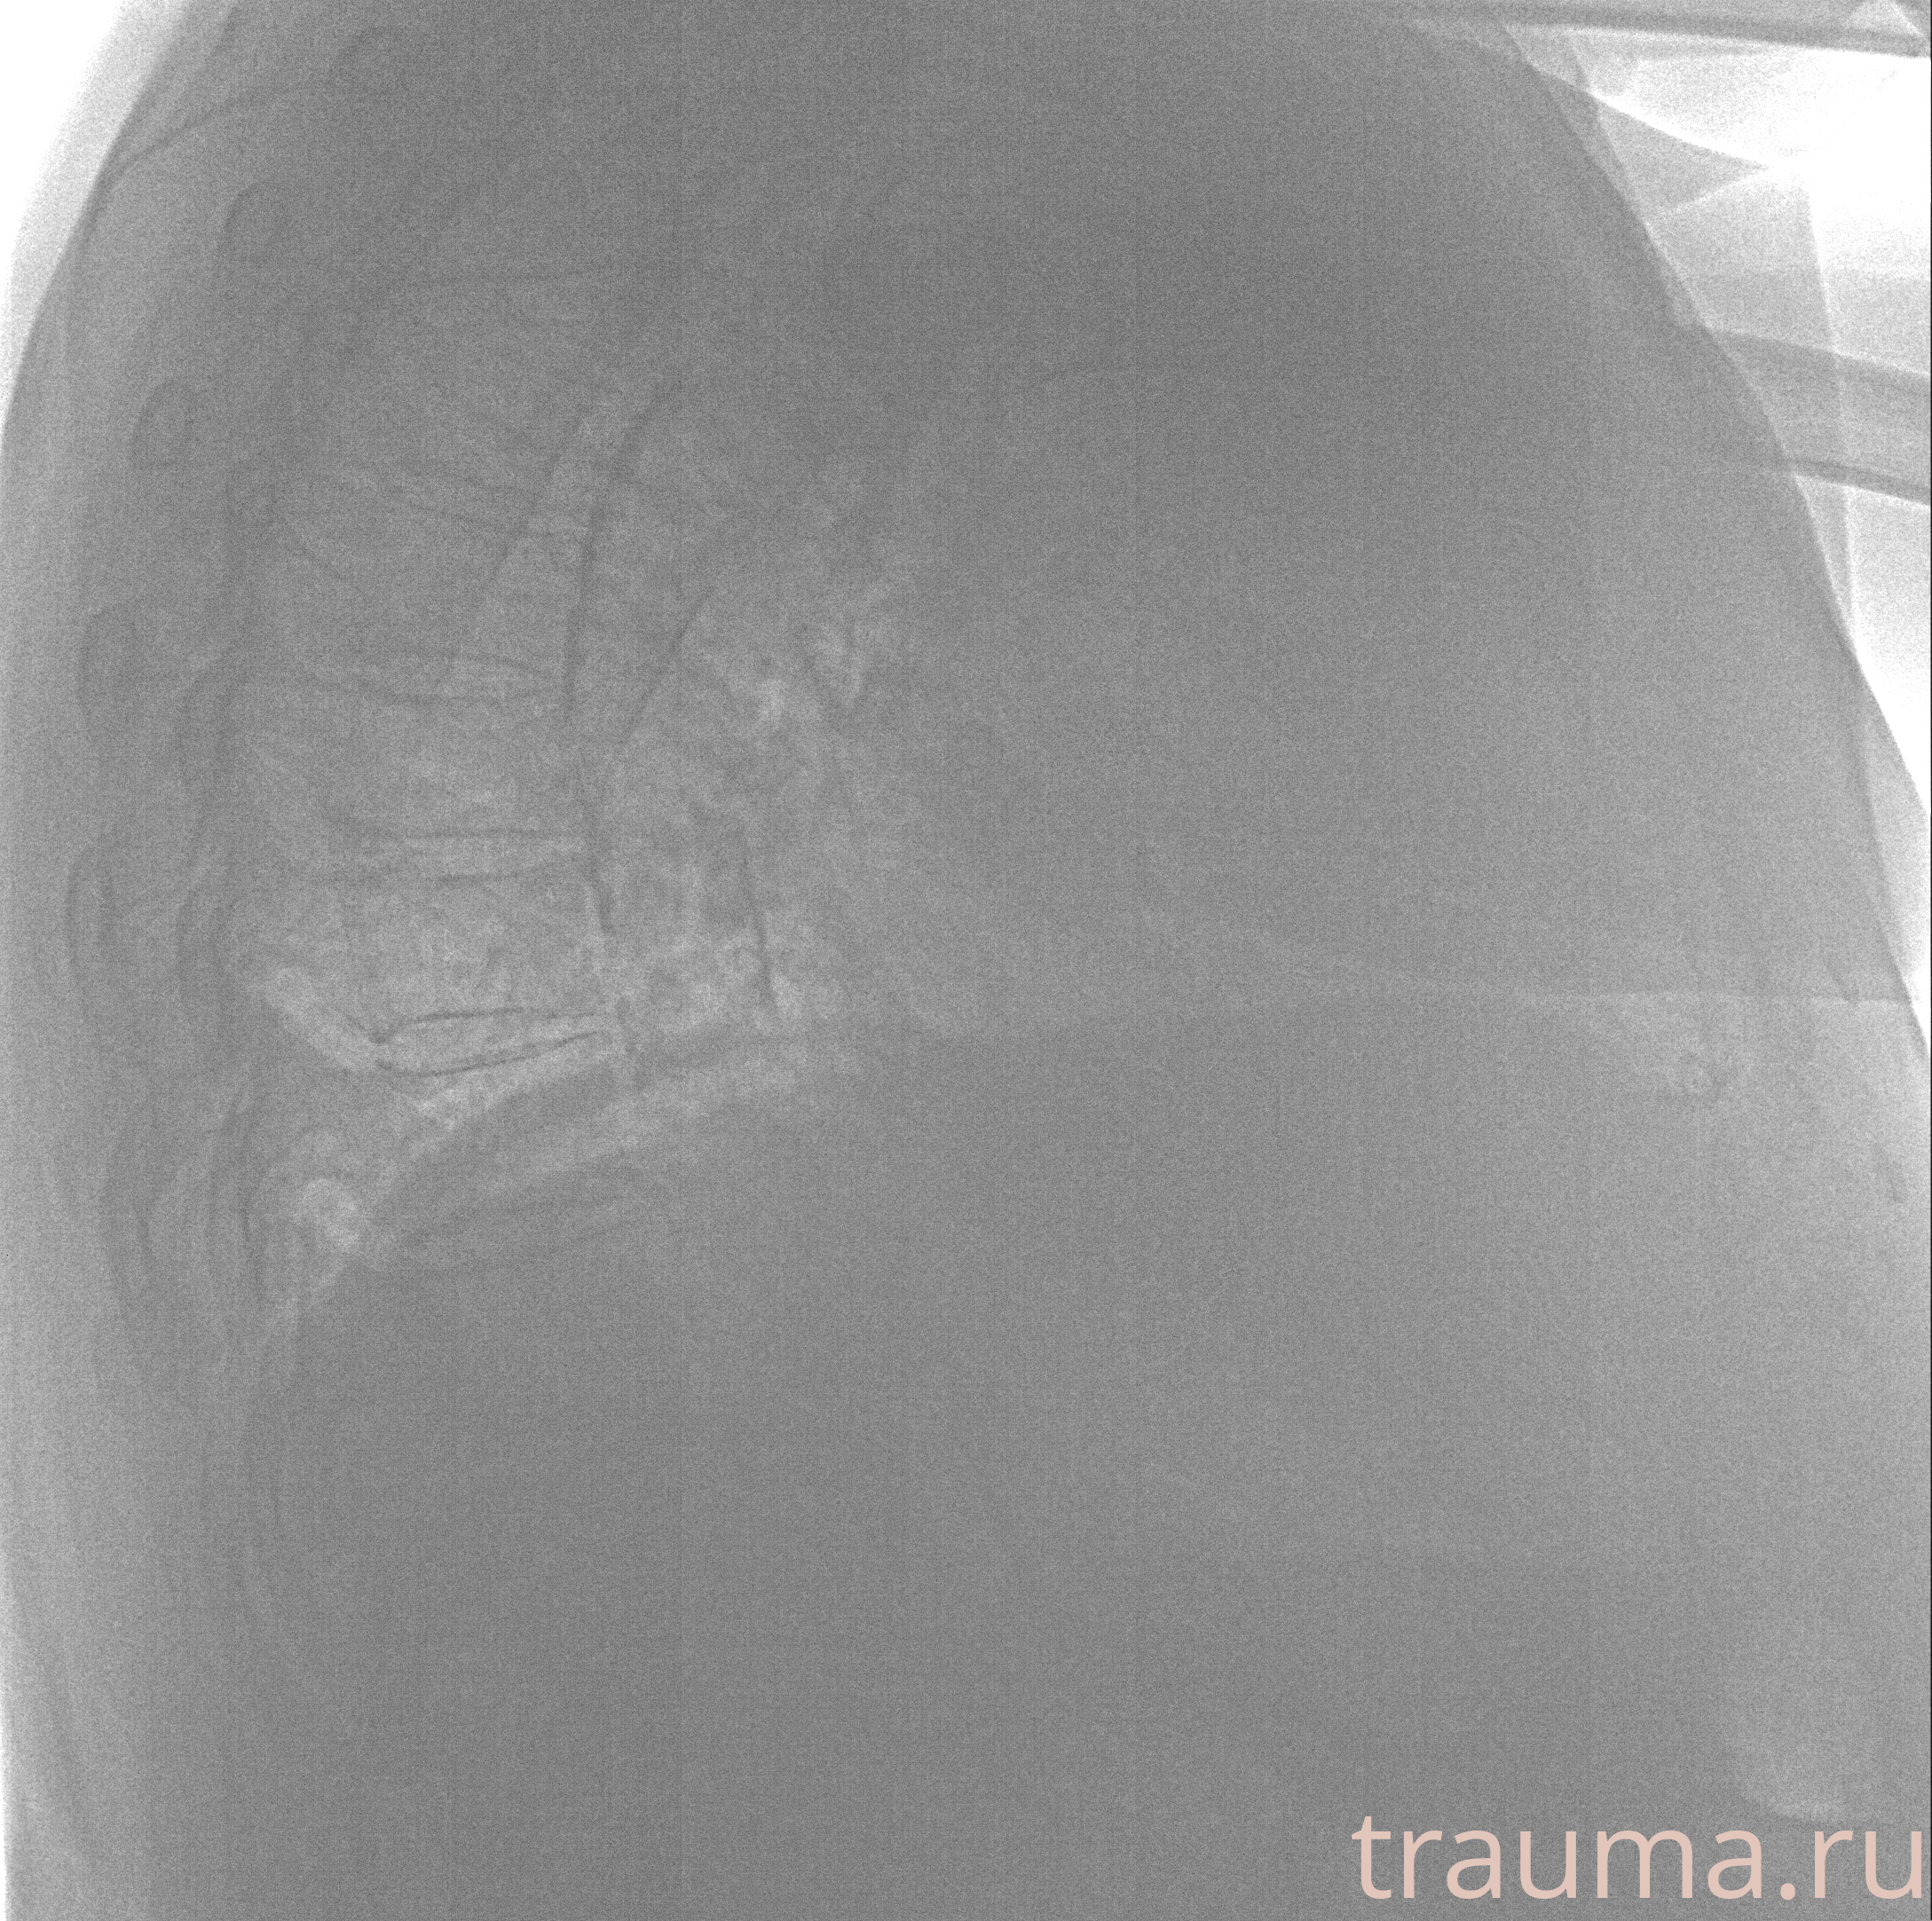

Рентгенограммы

Рентген на дому: по вашему адресу приезжает врач-рентгенолог, травматолог-ортопед с мобильным рентгеновским аппаратом, проводит диагностику травмы или заболевания, делает необходимые рентгенограммы, дает рекомендации по дальнейшему лечению. Получить качественные снимки в домашних условиях возможно благодаря уникальной методике, разработанной МосРентген Центром для института  Склифосовского